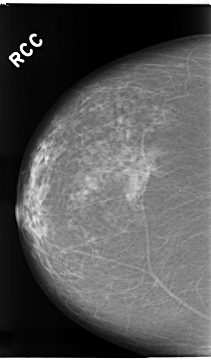

C_0112_1.RIGHT_MLO

C_0112_1.RIGHT_CC

RIGHT_CC LINES 4672 PIXELS_PER_LINE 2736 BITS_PER_PIXEL 12 RESOLUTION 50 NON_OVERLAY

RIGHT_MLO LINES 4664 PIXELS_PER_LINE 2880 BITS_PER_PIXEL 12 RESOLUTION 50 NON_OVERLAY